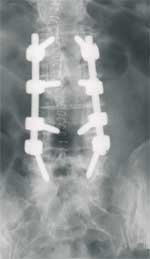

Hier, so soll das nachher ausschauen.

strempel-impl-roe.jpg

strempel-impl-roe.jpg (4.07 KiB) 6711 mal betrachtet

Am Schraubenkopf ist ein beweglicher Metallteil angebracht, durch welchen nach dem Einbringen der Schrauben in die Wirbel zwei Stäbe parallel zur Wirbelsäule eingeführt werden. Es müssen zur Stabilität mindestens vier Schrauben eingesetzt werden. Die Schraubenanzahl ist abhängig von jener der verformten und schmerzhaften Segmente. Dieses Schrauben-Stab-System wirkt wie ein inneres Korsett, erhält aber durch die dynamischen Schraubenköpfe die Elastizität der Wirbelsäule.

Das Einsetzen dieses dynamischen Implantats (Cosmic-System) dauert unter normalen Umständen zirka zwei Stunden. Durch eine besonders schonende Operationsmethode erholt sich der Körper schnell.